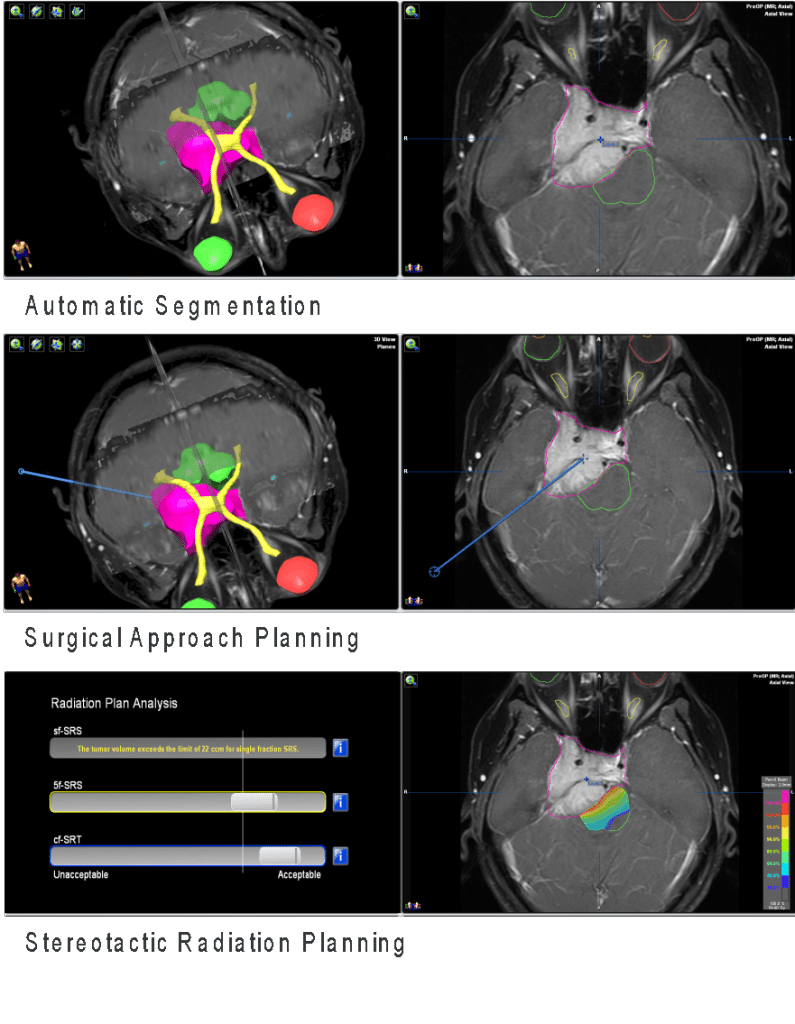

Dependendo da localização e extensão do tumor (como na base do crânio, por exemplo), expertise extra do cirurgião é necessária a fim de se ressecar a lesão com segurança. Em muitos casos, a monitorização da função cerebral ou de determinados nervos cranianos durante a cirurgia é essencial para se evitar danos a essas estruturas, o que pode causar surdez, desequilíbrio, paralisia da musculatura da mímica, paralisia da língua, dificuldade de engolir, falar, etc, etc.

Um volumoso meningioma de base de crânio (imagem branca à esquerda demonstrada na ressonância magnética), o resultado da cirurgia mostrando retirada completa da lesão na imagem do meio e a fotografia da paciente totalmente recuperada (lado direito), vivendo normalmente e sem sintomas.

Radiocirurgia

Em caso de pequenos restos tumorais após a cirurgia, ou naqueles casos onde o risco da cirurgia é estimadamente muito alto (seja por problemas de saúde do paciente ou localização profunda da lesão), pode-se tratar o tumor por meio de radiocirurgia, que é a aplicação em dose única de irradiação ionizante, de maneira não-invasiva, a fim de se controlar o crescimento do tumor. Um dos aparelhos mais modernos para esse fim é o Gama-Knife, disponível no Hcor, em São Paulo. Nessa forma de tratamento, o feixe de irradiação é direcionado ao tumor por diversos ângulos, com precisão sub-milimétrica, poupando-se as estruturas vizinhas da radiação.

Plano de tratamento radiocirúrgico para um meningioma da base do crânio, onde poupa-se as vias visuais e o tronco encefálico de doses excessivas de radiação.